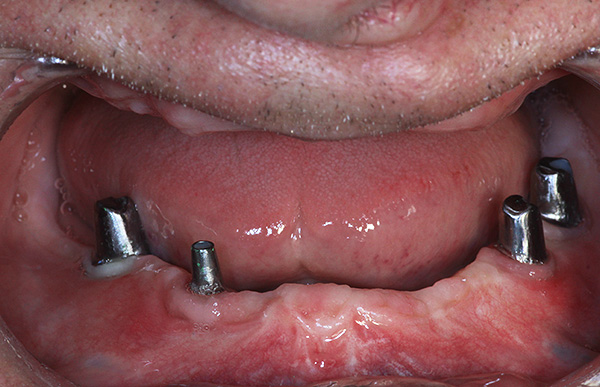

Geralmente, para "núcleos" da categoria de risco, o dentista escolhe um implante basal, que é realizado em um curto período de tempo (por 3-5 dias). Com algumas das suas desvantagens, esse tipo de colocação de implantes permite reduzir o tempo gasto pelo paciente enfraquecido na cadeira e rapidamente retorna à vida normal e plena da sociedade.